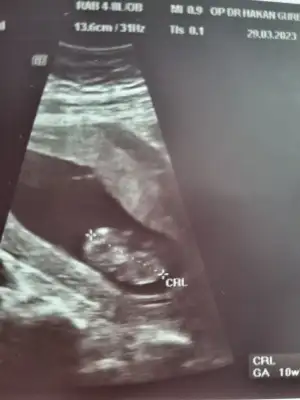

Merhaba 11+4 olduk bugün 🙏🏻 aranızda ultrason görüntüsünden cinsiyet anlayan var mı acaba ☺️ ultrasonda bakarken kafası böyle değildi daha yuvarlaktı ama bilemiyorum ben bakınca erkek diyorum ama içimden kız geçiyor 🥰

• CB0BD7F6-FB00-4316-8652-9D6188BB00BD.webp

CB0BD7F6-FB00-4316-8652-9D6188BB00BD.webp

18,6 KB · Görüntüleme: 92